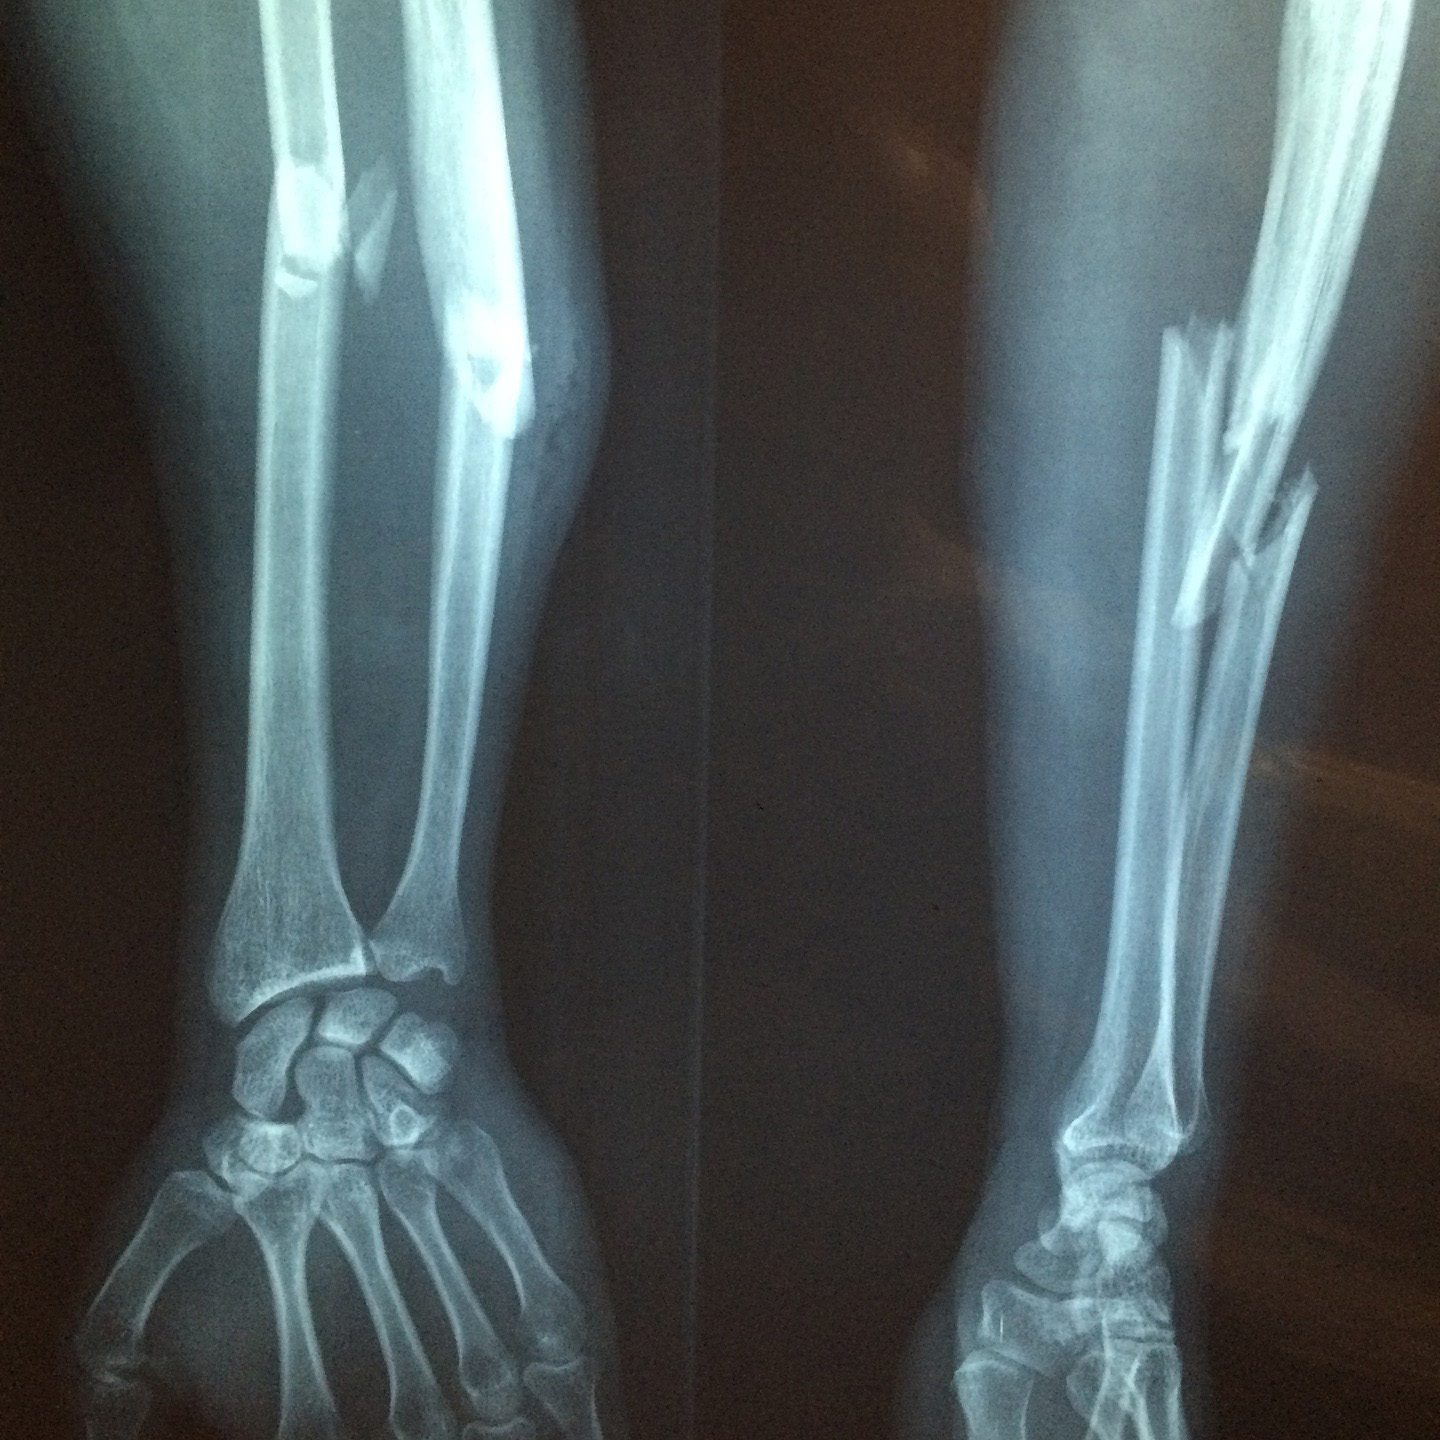

10. Fall safely: If you do fall, try to stretch out your hands to break your fall and avoid fracturing your hip or spine.